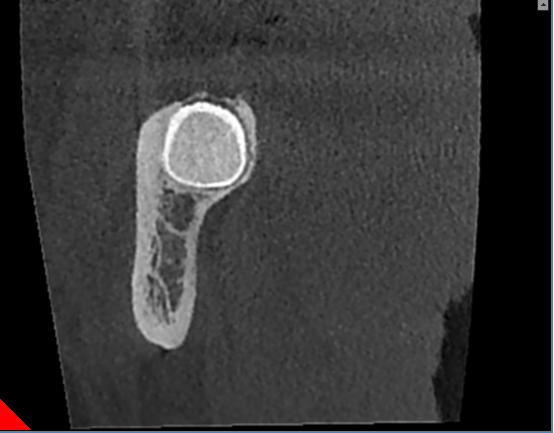

残根

颌面外科扫描能精确展示特定解剖特点,如囊肿或牙断裂,深度牙根形状和倾斜度。